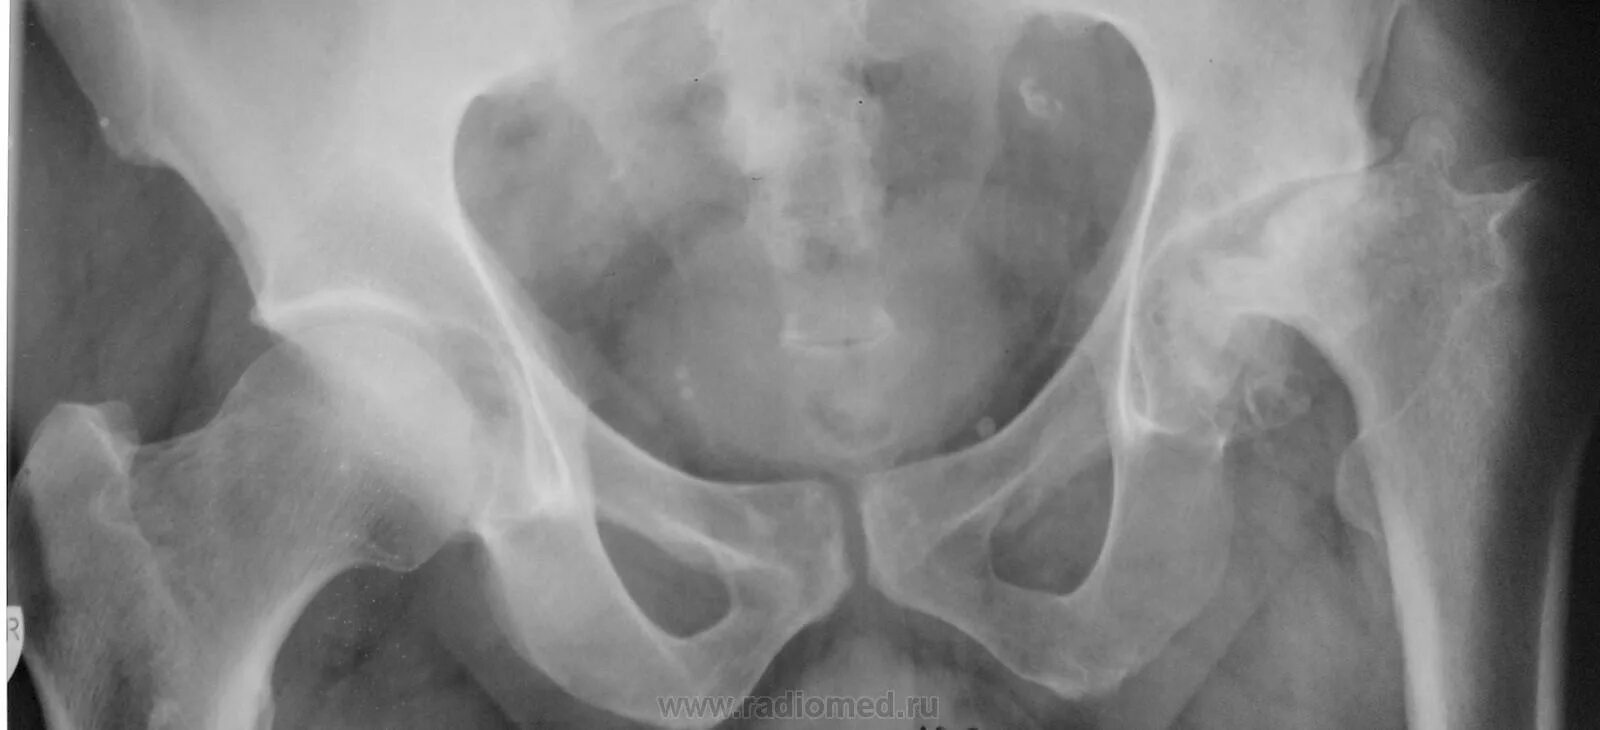

Анкилоз тазобедренного сустава